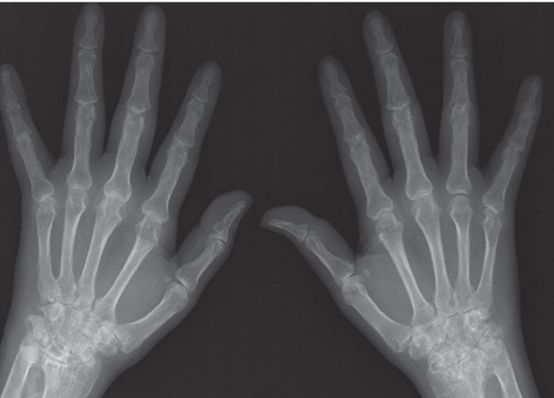

实验室结果如下:红细胞沉降率91 mm / h,C反应蛋白2.69 mg / dL,白细胞3,110 /μL,血红蛋白9.6 g / dL,血小板190,000 /μL,抗核抗体1:40(混合均质和斑点图案),抗dsDNA抗体14.2 IU / mL,类风湿因子98 IU / mL和抗CCP抗体> 300 U / mL。此外,血清补体水平降低,C3 62 mg / dL,C4 6.20 mg / dL,直接Coombs检测阳性。尿蛋白/肌酐比率为561.93 mg / g。然而,抗心磷脂、抗β2糖蛋白1和狼疮抗凝血抗体均为阴性。双手平片显示关节周围骨质减少,关节间隙狭窄,MCP、PIP和腕关节边缘糜烂(图2)。

图2双手平片显示近端指间关节2 ~ 5关节间隙狭窄,掌指关节、腕关节1 ~ 5关节边缘糜烂,关节间隙狭窄,双侧关节周围骨质减少。